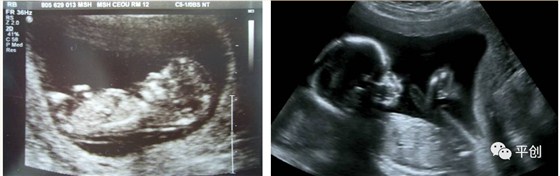

更準(zhǔn)確的醫(yī)學(xué)診斷,來自B超檢查結(jié)果的輔助,準(zhǔn)確的B超檢查結(jié)果,來自B超醫(yī)生看到的B超圖像,清晰的B超成像,來自好的耦合劑。所以說,好的耦合劑對(duì)B超的成像很重要。

而影響B(tài)超檢查成像的因素有兩點(diǎn),一是來自好的探頭,二是來自優(yōu)質(zhì)的耦合劑。如果這兩個(gè)產(chǎn)品其中有一個(gè)質(zhì)量不過關(guān),即對(duì)B超成像有一定程度的影響,可能會(huì)有成像不清楚,醫(yī)生無法準(zhǔn)確判斷所檢查器官的實(shí)際病變,嚴(yán)重的有可能度至醫(yī)生誤診的后果。

普通的卡波姆,其透聲力沒達(dá)到超聲波傳導(dǎo)的系數(shù),無法有效地傳達(dá)聲波,同時(shí)沒有良好的偶合功能,這種情況下,就無法形成清晰的圖像。

另外,有的廠家的耦合劑濃度太高,或是太稀,涂在檢查部位上,馬上就有一部分水流出,讓患者感到很不舒服,而過稀的耦合劑會(huì)減低其偶合性,過濃的耦合劑難以展開涂抺,或涂抺不均勻,影響探頭在檢查部位的滑動(dòng),這兩種情況都會(huì)減低B超中的耦合性,影響B(tài)超成像的清晰度,從而影響醫(yī)生看到的結(jié)果而給出錯(cuò)誤的判斷,甚至間接的引發(fā)了醫(yī)療事故,嚴(yán)重地影響了醫(yī)院的專業(yè)度和信服力。這些都是醫(yī)生和醫(yī)院及患者都不希望發(fā)生的。

所生產(chǎn)出來的耦合劑無雜質(zhì)、透明度高、不易干,不化水,易偶合、易擦凈,透聲性超過國家標(biāo)準(zhǔn)的50%(數(shù)據(jù)通過國家指定的第三方檢測機(jī)構(gòu)檢測結(jié)果所得),完全地解決了成像不清晰的難題。